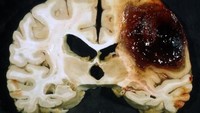

Contoh otak stroke yang terjadi karena ada pembuluh darah pecah di bagian basal ganglia. (Foto: neuropathology-web.org)